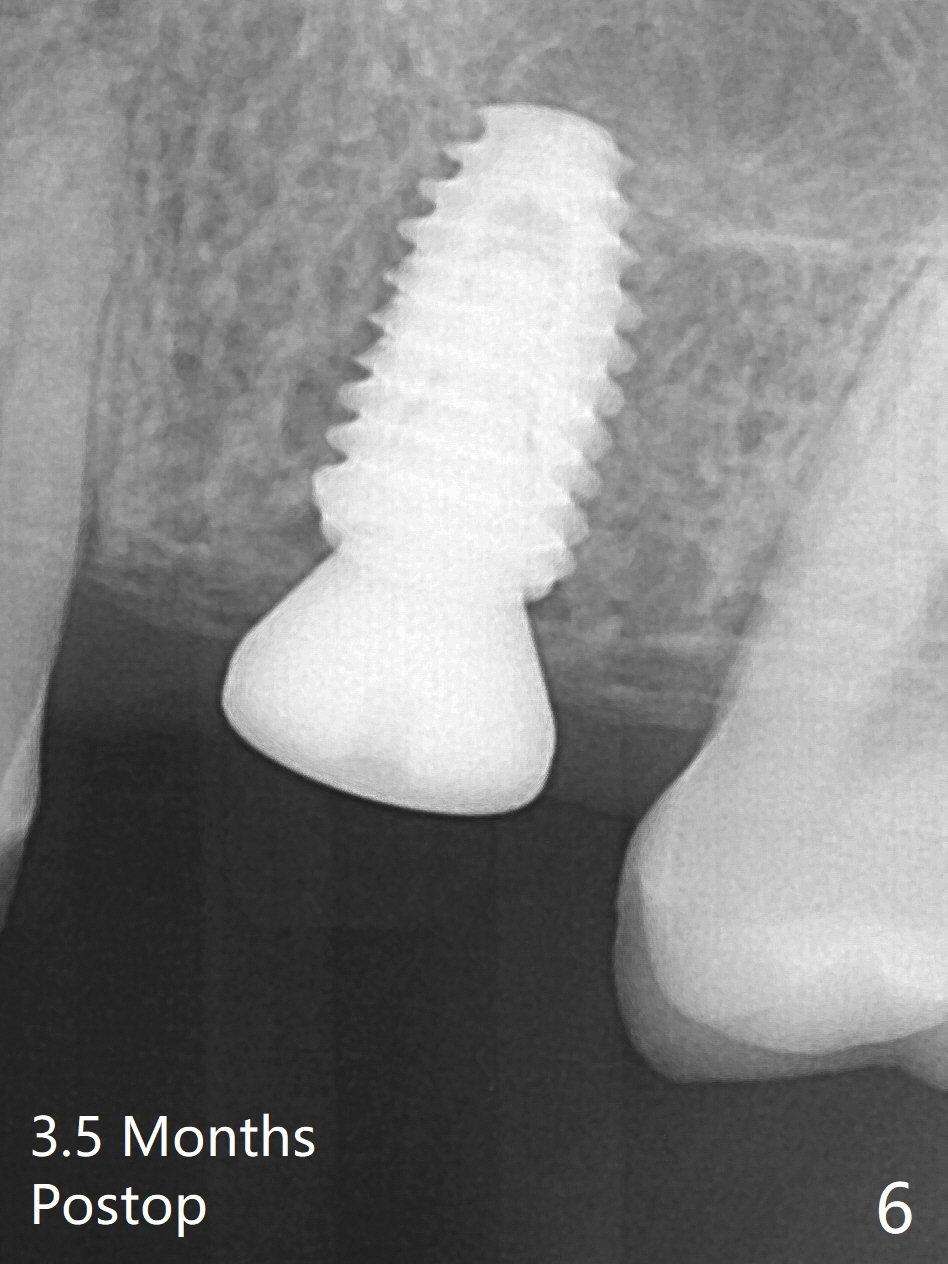

The guide is removed when the osteotomy at #14 (Fig.1 (8.45 mm bone height)) is finished in an under drilling manner in depth (Fig.2). The middle of the apical remaining bone is so thin (Fig.3 (white line representing the sinus floor)) that it can be pushed up like ping pong or eggshell (Fig.4 arrow). A 5x8.5 mm implant is placed with satisfactory insertion torque and depth, followed by insertion of a 6x3 mm healing abutment (Fig.5). There is mild resorption of the sinus floor distally 3.5 months postop, although the implant remains stable (Fig.6).